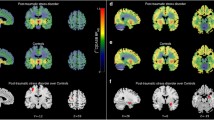

Table 1 gives an overview of the demographic and clinical variables of the study participants. There were no statistically significant differences in age, gender, and smoking status between patients and controls (all p > 0.19). Severity of state anxiety (STAI) was significantly increased in patients suffering from UMD or OCD compared with healthy control subjects (two sample t test: t = 5.31, df = 36, p < 0.0001). In patients (UMD or OCD), thalamic 5-HTT BPND (1.10 ± 0.23) was reduced by about 20% (controls: 1.36 ± 0.18; two sample t test: t = 4.05, df = 38, p < 0.0001; controlling for age, gender, smoking status, seasonality, and genotype: t = 3.45, df = 30, p < 0.001; Fig. 1). Thalamic 5-HTT BPND was not associated with time since last selective serotonin uptake inhibitor intake measured in plasma half-lives (p = 0.47). In the voxelwise analysis, using a voxel-level threshold of p = 0.01, we found a single cluster (8.1 ml) that was predominantly located in the bilateral thalamus (where we found the maximum t value Tmax = 4.0 at MNI 6/−22/6), and included adjacent parts of the midbrain (where we found the maximum contrast at MNI −2/−24/−2). This cluster survived SPM's correction for multiple comparisons (p < 0.05 FWE corrected). No voxels outside this cluster met the threshold of p < 0.01.

Group differences in 5-HTT levels. Top: ROI analysis shows reduced serotonin transporter levels binding potential (BPND) in the thalamus of 20 subjects with negative mood states versus 20 matched healthy controls, measured with PET and the radioligand [11C]DASB. Bottom: Voxelbased analysis (SPM2&MASCOI) shows a large cluster extending from the midbrain to the bilateral thalamus, surviving correction for multiple testing (p < 0.05 FWE corrected). UMD indicates patients suffering from unipolar major depression, OCD indicates obsessive–compulsive disorder, and control indicates healthy controls